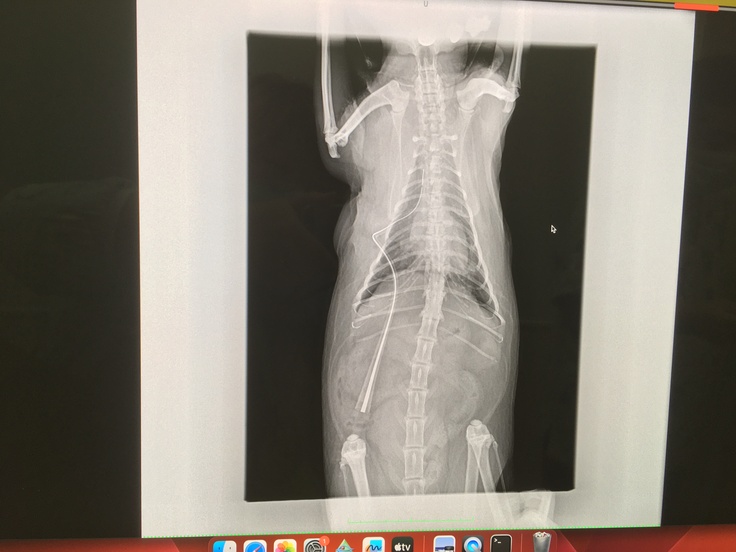

10月15日(日)13:00~16:00 肺腺瘤(肺腺癌の疑い)を摘出手術を行いました。

手術後、右肺の中葉に出来た腫瘍が綺麗にとれました。

右肺腺瘤に膿瘍もあったそうですが、綺麗に取れたとのこと。

獣医師より『肺腺瘤はギリギリ癒着もなく、綺麗に取ることが出来ました、肺腺瘤に膿瘍も付着し発見したけど、薄皮一枚で繋がっており体内で破裂してなかったのが幸いで、それも全て取れた』と仰っていただきました。

↑術後の画像、綺麗に肺腺瘤、膿瘍が摘出して頂いてます。

肥大型心筋症、大動脈血栓塞栓症の大きな爆弾は抱えていますが、肺腺瘤摘出により呼吸が楽になる選択を1つ得ることが出来ました。